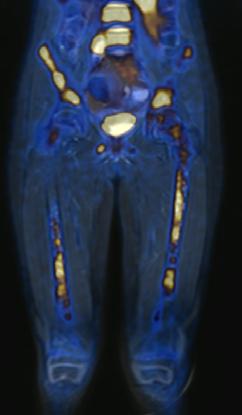

Estudio PET con 6-[18F]DOPA 3A) y [18F]OCTREOTIDE 3B) en cortes coronales de secuencias T2 de miembros pélvicos y con imágenes fusionadas, donde se identifica mayor sobreexpresión anormal de los receptores de somatostatina al compararlos con 6-[18F]DOPA, y que hace candidata a la paciente para PRRT.

Femenino de 7 años con diagnóstico de Neuroblastoma, se realiza PET/RM con [18F]F-DOPA para estadiaje, con evidencia de lesión primaria a nivel de retroperitoneo y conglomerados locoregionales así como infiltración a médula ósea del esqueleto axial y apendicular (Figura 1A), posteriormente la paciente fue tratada quirúrgicamente con resección de la lesión primaria así como tratamiento con inmunoterapia y transplante autólogo de médula ósea además de radioterapia. Al presentar refractariedad al tratamiento comentado, se plantea la posibilidad de administrar Lutecio (177Lu) oxodotreotide, por lo que se sugiere realizar PET/RM con [18F]Octreotide para valorar expresión de receptores de somatostatina y considerar la terapia con radionúclidos para receptores de péptidos (PRRT), el estudio muestra evidencia de sobreexpresión anormal de dichos receptores en retroperitoneo, espacio subpleural izquierdo además de esqueleto axial y apendicular (Figura 1B).

Al correlacionar con 6-[18F]DOPA (Figura 1A) se observa que las lesiones tienen mayor sobreexpresión de los receptores de somatostatina.